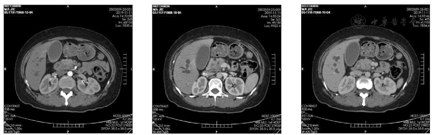

胰腺三期增强64层螺旋CT:胰头钩突区占位,考虑胰腺癌、低位胆道梗阻(图1)。